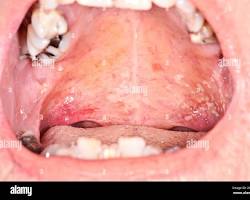

- Canker Sores:

Canker sore on the roof of the mouth